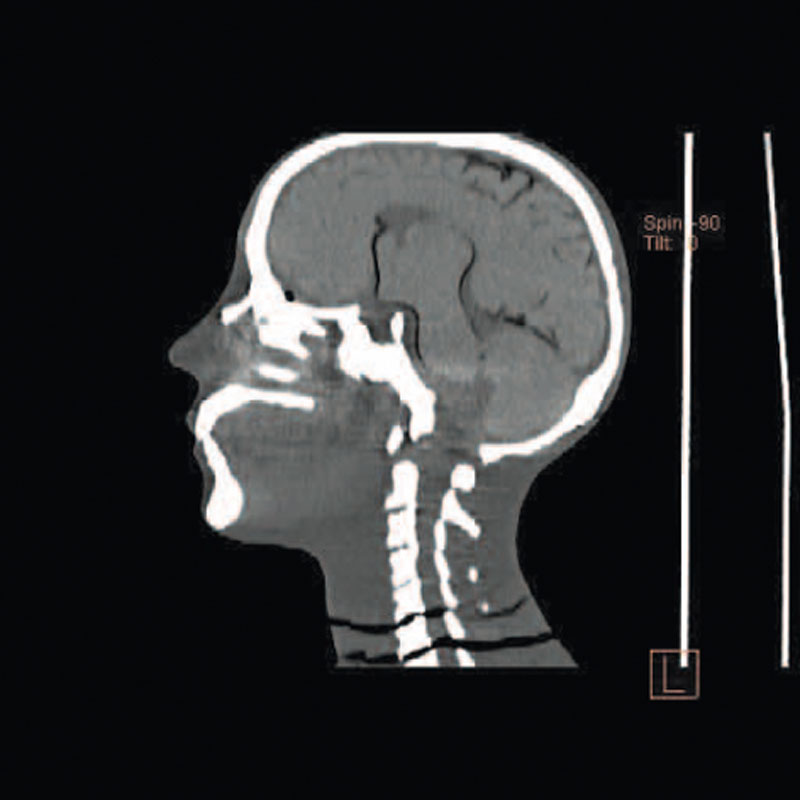

Ein einzigartiges Ganzkörperphantom für CT bietet eine Vielzahl von Ausbildungs- und Forschungsmöglichkeiten. Das Phantom kann auch für normales Röntgen benutzt werden und gibt lebensnahe Bilder. Es benden sich keine Metallteile oder Flüssigkeiten im Phantom. Die wichtigen Gelenke haben eine menschenähnliche Beweglichkeit und erlauben vielfältige Positionen für die Übung. Das Phantom kann in 10 Teile zerlegt werden. Die verbesserten Schultergelenke erlauben es, die Arme nach oben zu bewegen. Die künstlichen Organe sind anatomisch korrekt und haben entsprechende HU-Zahlen.

- Synthetischer Schädel

- Halswirbel

- Gehirn

Radiologische Absorption und Hounsfield-Nummer ähnlich dem menschlichen Körper.